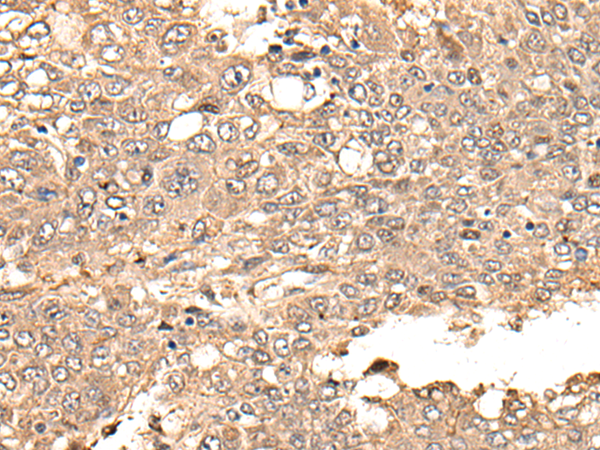

IHC positive control: |

Human liver cancer |

IHC Recommend dilution: |

25-100 |